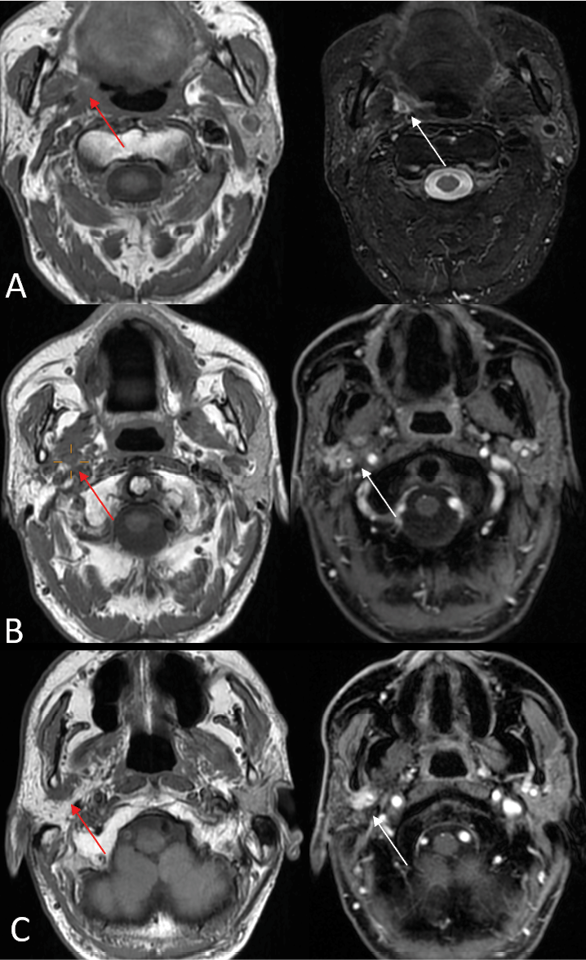

3) Obliteration of Fat Planes and pterygopalatine fossa (Fig. 4 C). In Perineural Spread (PNS), tumor invasion can disrupt and replace the normal fat planes surrounding nerves, which serve as a natural barrier visible on imaging. This obliteration, often seen as a loss of the normal hypodense fat signal on CT or the hyperintense fat signal on MRI T1 sequences, indicates tumor infiltration or extension, aiding in the diagnosis of PNS [2].

Fig. 3. PNS in the branches of the mandibular nerve. On the left side: T1-weighted imaging; on the right side: T1-weighted imaging with fat suppression and contrast enhancement. A – Tumor spread is observed in the left parapharyngeal space, where the normal hyperintense fat signal (as seen on the left) is replaced by hypointense tumor masses (the red arrow). The tumor exhibits contrast enhancement (the white arrow). B – PNS changes in the mandibular nerve region, showing thickening and contrast enhancement of the mandibular nerve within the masticatory muscle compartment (the red arrow). The nerve enhances with contrast (the white arrow). C – PNS is observed in the auriculotemporal nerve region, showing thickening, and hypointensity (the red arrow) and contrast enhancement (the white arrow) in the retromandibular area.